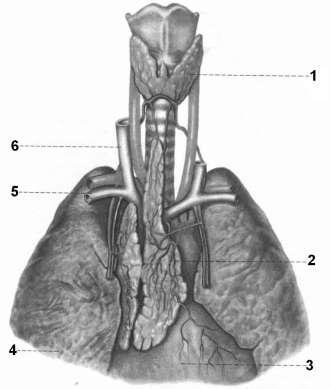

Фотографии вилочковой железы тимуса: структура и функции